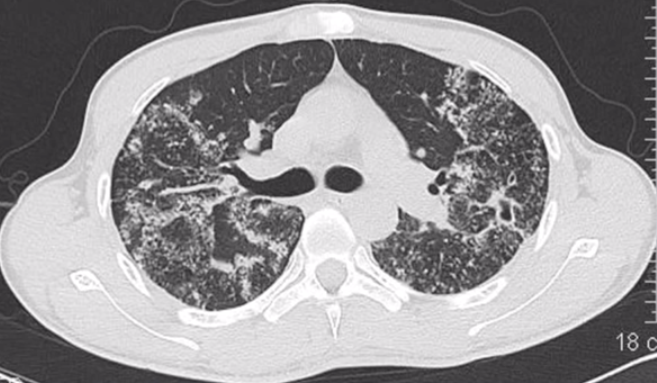

反晕征伴小结节、树芽征,指示肺结核

图源:张嵩《诊断必备:肺部 CT 的诊断技巧及误区》

以反晕征为主要表现的肺结核患者,多为年轻患者,病情较轻,病灶主要分布在上肺,可有小结节、树芽征并存。本病例即肺结核,CT 表现主要为反晕征,伴随有小结节、树芽征,抗结核治疗后好转。